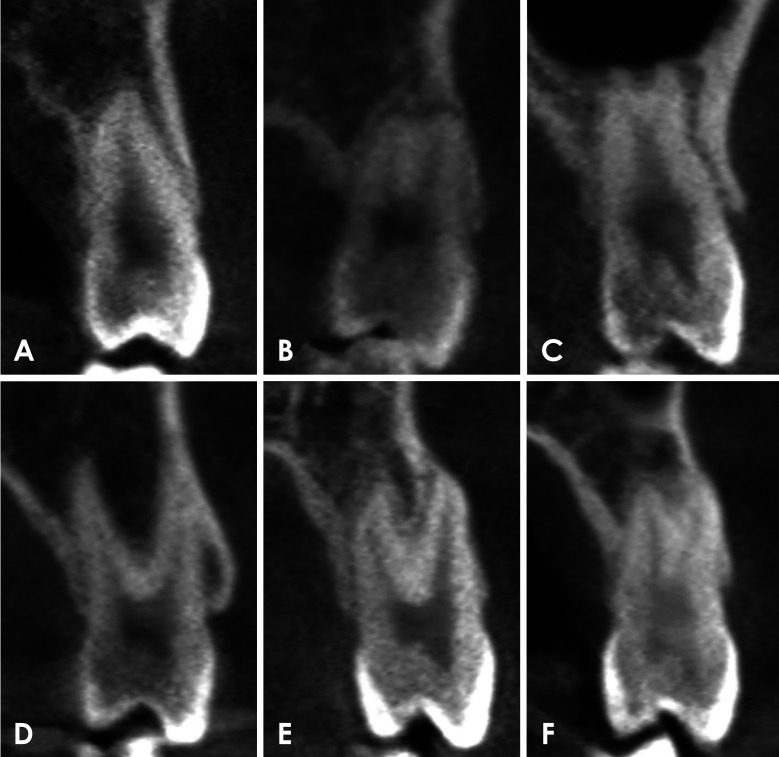

Purpose: This study aimed to evaluate the number of roots and type of root canals in maxillary first and second premolars within a selected Korean population utilizing cone-beam computed tomography (CBCT). Additionally, it sought to investigate potential differences in these features according to sex and tooth type.

Materials and methods: CBCT images of 585 maxillary first premolars and 578 maxillary second premolars from 303 patients were retrospectively reviewed. The number of roots was classified based on root morphology, and canal configurations were categorized into 8 types according to the Vertucci classification. For statistical analysis, chi-square or Fisher exact tests were employed to compare root number and canal morphology according to sex and tooth type.

Results: CBCT analysis revealed that 71.5% of maxillary first premolars and 97.6% of maxillary second premolars had 1 root. The most common canal configuration in maxillary first premolars was Vertucci type IV (42.6%), whereas type I predominated in maxillary second premolars (76.5%). Significant differences in root number and canal configurations were found between men and women (P<0.05), with single roots and Vertucci type I canals more commonly observed in women.

Conclusion: Both maxillary first premolars and maxillary second premolars typically had 1 root, with a smaller percentage possessing 2 roots. Significant sex differences were observed in root number and canal type. This study highlights the variability in root number and canal configuration, emphasizing the importance of recognizing these variations to achieve successful endodontic treatment.